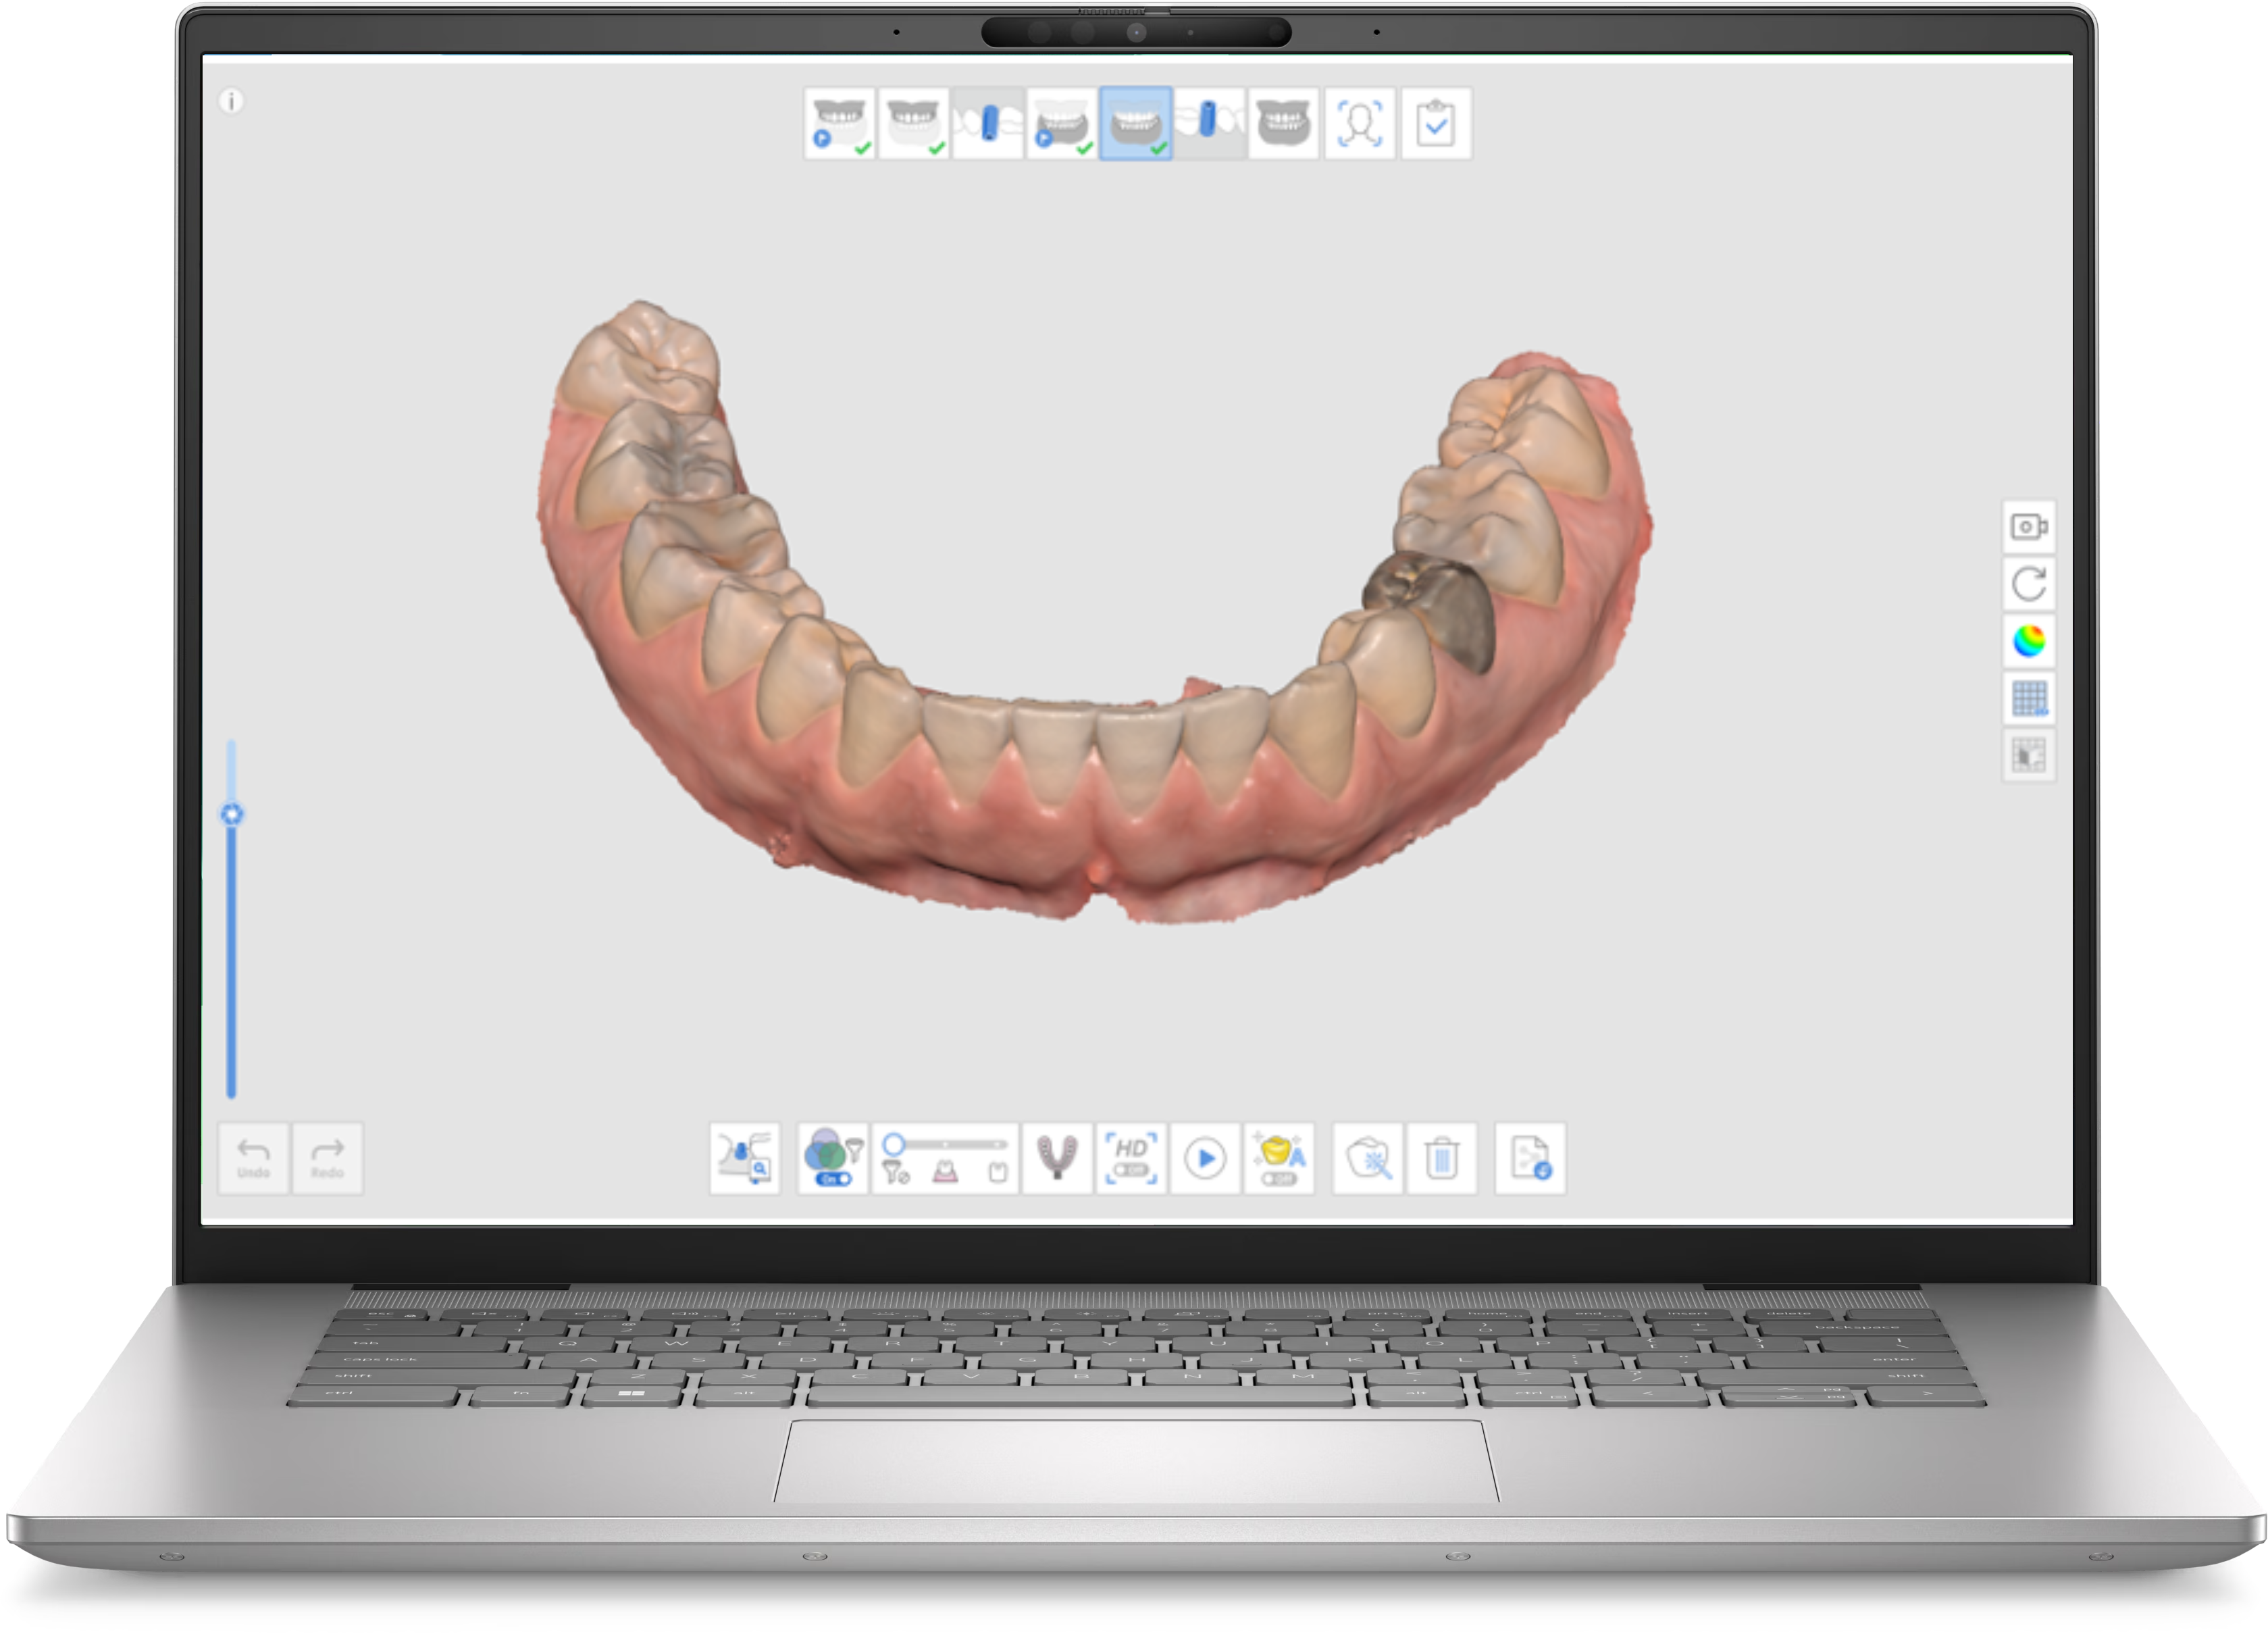

Scanerele intraorale utilizează lumina pentru a captura imagini tridimensionale ale dinților și gingiilor. Dispozitivul emite un fascicul luminos care este reflectat de suprafețele dentare, iar senzorii din scanner detectează aceste reflexii. Datele sunt procesate în timp real pentru a crea o imagine 3D detaliată a cavității orale. Aceste imagini pot fi folosite pentru diagnostic, planificare de tratament și fabricarea dispozitivelor dentare, cum ar fi coroane, punți și alignere ortodontice.

Scannerul Medit i600 reprezintă una dintre cele mai recente inovații în domeniu, combinând performanța înaltă cu accesibilitatea. Acesta oferă o acuratețe de 10.9 μm și o viteză de scanare de până la 35 FPS, fiind capabil să gestioneze diverse tipuri de scanări, inclusiv arcadă completă, segmente și implanturi. Designul ergonomic și greutatea redusă de doar 245 de grame îl fac ușor de utilizat, reducând oboseala utilizatorului și îmbunătățind confortul pacientului.

Medit i600 este capabil să gestioneze diverse tipuri de scanări, inclusiv scanări de arcadă completă, scanări de segmente și scanări pentru implanturi. Această versatilitate îl face ideal pentru o gamă largă de proceduri stomatologice, de la restaurări până la ortodonție